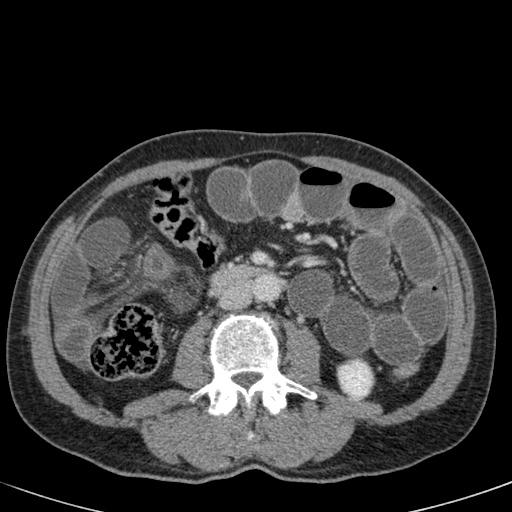

Đây là một bệnh nhân bị tắc ruột non.

Cuộn qua các hình ảnh.

Bạn có thể tìm thấy quai kín và nguyên nhân gây ra nó không?

Khi tiếp nhận bệnh nhân tại phòng cấp cứu với biểu hiện nghi ngờ tắc ruột non (SBO), điều quan trọng nhất chúng ta cần làm, ngoài việc chẩn đoán xác định, là xác định sự hiện diện hay vắng mặt của tình trạng thắt nghẹt.

Hình ảnh CT của tắc ruột non dạng quai kín phụ thuộc vào hai yếu tố:

- chiều dài đoạn ruột tạo thành quai kín

- hướng của quai ruột so với mặt phẳng tạo ảnh

Nếu quai kín ngắn và nằm trong mặt phẳng tạo ảnh, chúng ta sẽ thấy quai ruột hình chữ U hoặc chữ C.

Tắc ruột dạng quai kín với các quai ruột giãn xếp theo hình nan hoa. Có dày thành ruột và phù nề mạc treo gợi ý thiếu máu cục bộ

Một hình ảnh quan trọng khác của tắc ruột dạng quai kín là các quai ruột non giãn xếp theo hình nan hoa với các mạch máu mạc treo hội tụ về một điểm trung tâm.

Hình ảnh này hầu như luôn do xoắn ruột non gây ra.